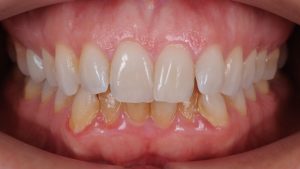

INITIAL

22 Semanas de Tratamiento